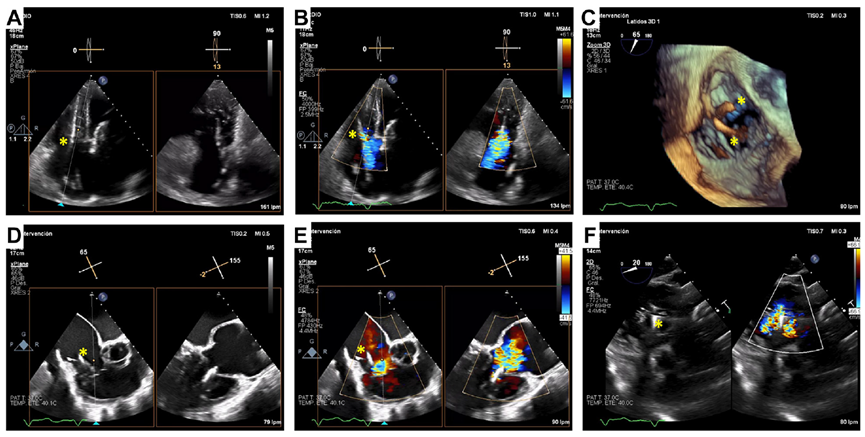

術(shù)后經(jīng)食道超聲,僅微量瓣周漏